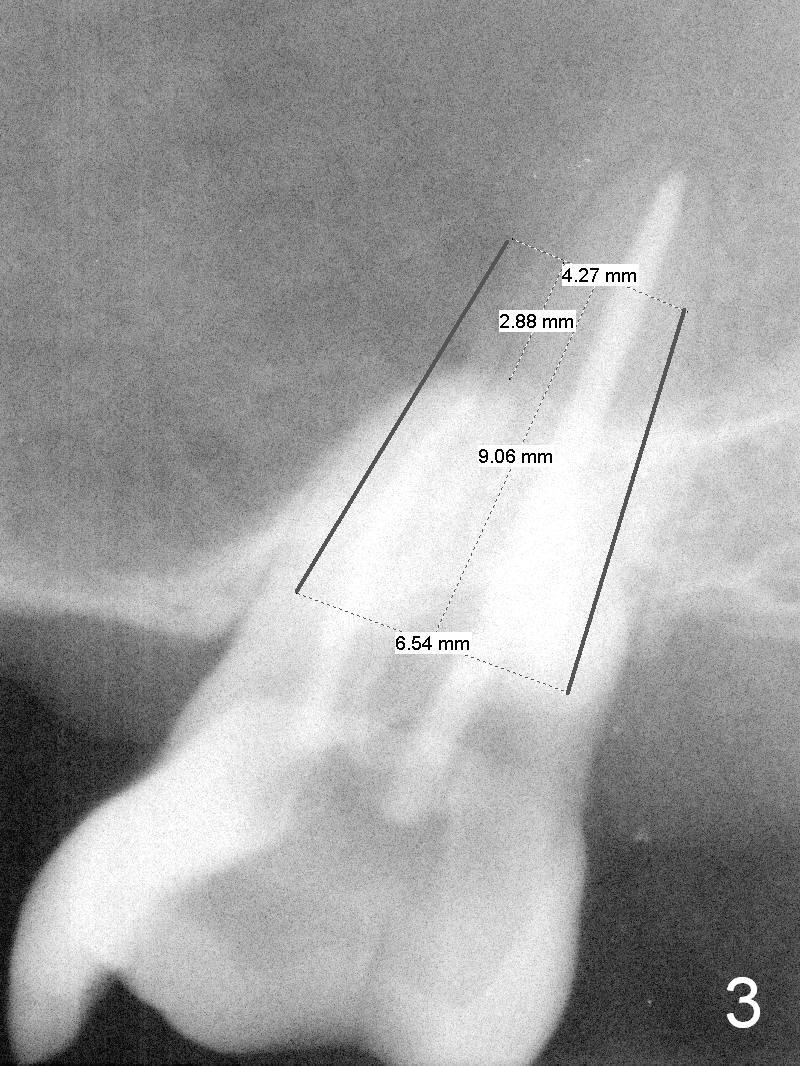

A 60-year-old man requests implant at #15, since the tooth with distal subgingival caries has kept fracturing in the last 4 years (Fig.1,2). Metronidazole will be used for socket disinfection. Since the socket is most likely large and single (fused roots), a large IBS implant (Fig.3,4: 6 or 6.5x9 or 11 mm) is to be placed following initial 7 mm depth of drilling or bone expansion (Fig.4). Prepare bone graft for sinus lift and gap closure. His bone is soft at #10; underprep is necessary at #15. An abutment is expected to be 6x4(3) mm (Fig.4). Since he is partially edentulous, an immediate provisional should be large enough to close the socket, but small enough not to be interfered with the partial denture on and off. Take photos of #10 to show no metal show.